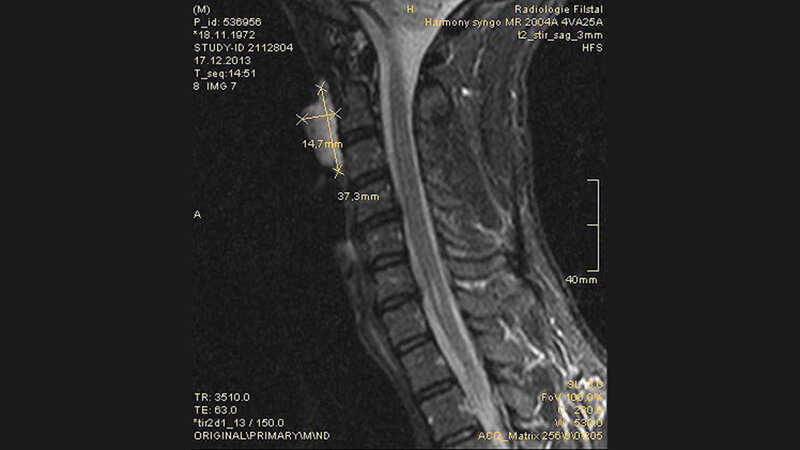

Schnittbilddiagnostik der Wirbelsäule (7.18)